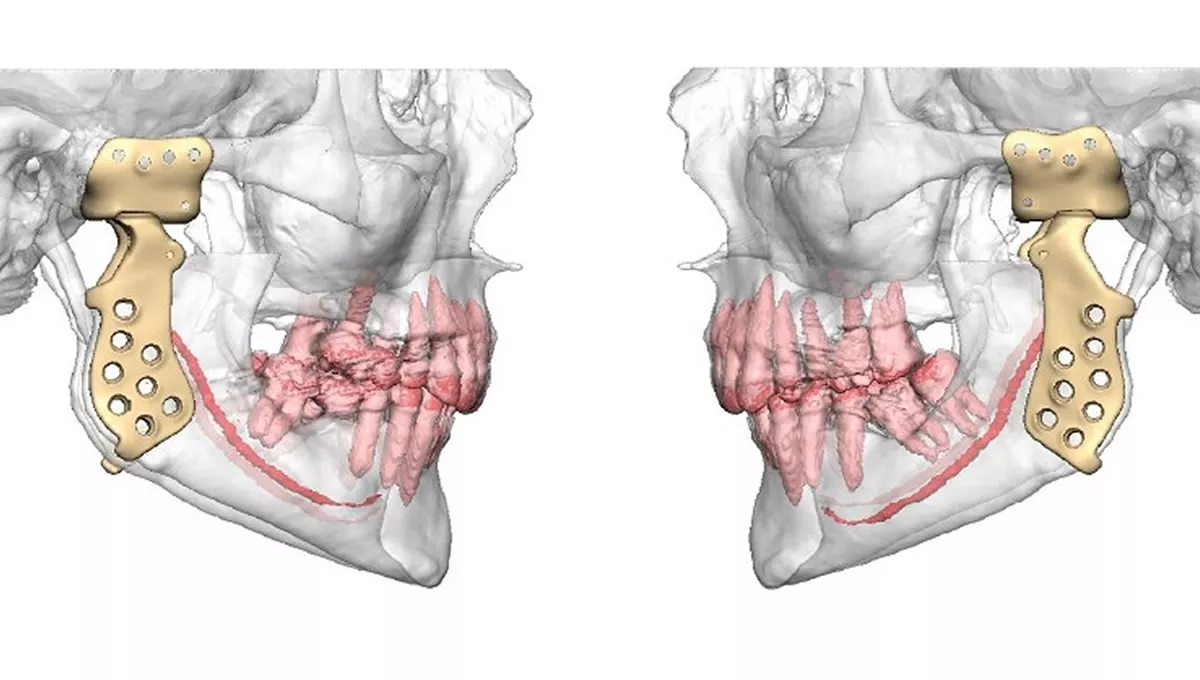

La planificación de esta compleja cirugía se inició en agosto de 2023 mediante videoconferencias, con la colaboración de una empresa gijonesa especializada en la producción de prótesis y material quirúrgico. La fabricación de las prótesis se basó en una reconstrucción tridimensional de una tomografía computarizada, diseñada en colaboración con expertos de Estados Unidos.

La fabricación de las prótesis se basó en una reconstrucción tridimensional de una tomografía computarizada

El trabajo previo permitió construir unas guías quirúrgicas para realizar las secciones del hueso que afectaban a las articulaciones. Seguidamente, se insertaron las prótesis realizadas a medida, que facilitaron un ajuste perfecto. La organización ha sido tan precisa que se calcularon las longitudes de todos los tornillos empleados, con el fin de evitar lesiones sobre estructuras adyacentes.